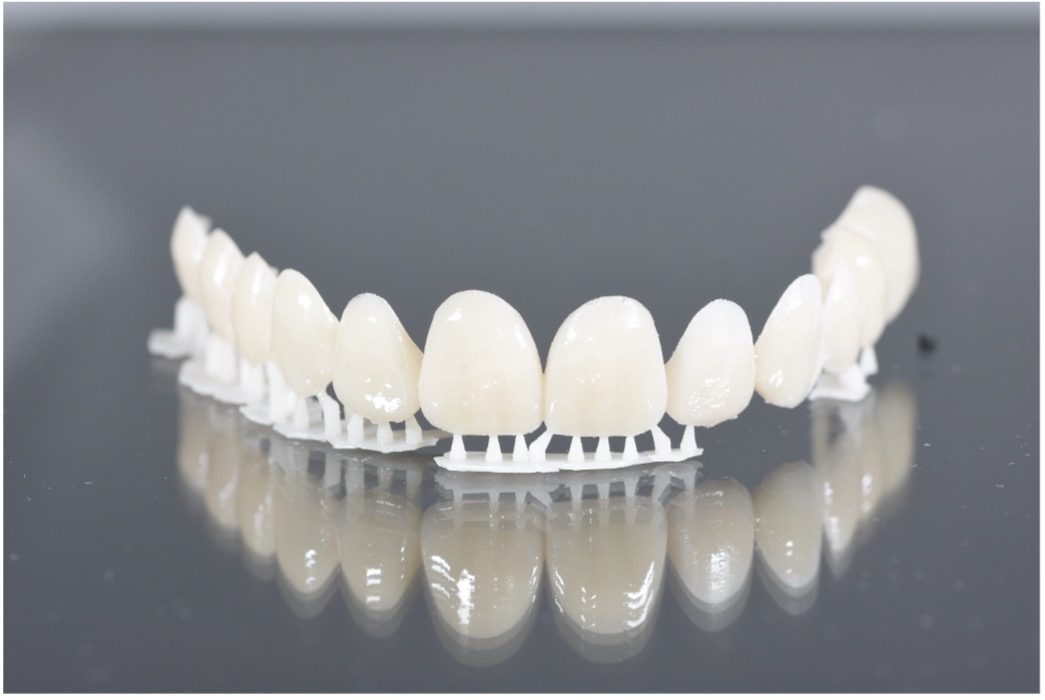

Once the digital design was approved, a physical mockup was created using resin for 3Dprinted materials. This mockup served as a test-drive for the proposed outcome, enabling real-time evaluation of the smile design in terms of esthetics, speech, and occlusion. The mockup was fitted in the clinic and reviewed from multiple angles, with special attention given to the patient’s reaction and comfort. Adjustments were made accordingly, allowing for refinements before any irreversible procedures were performed.